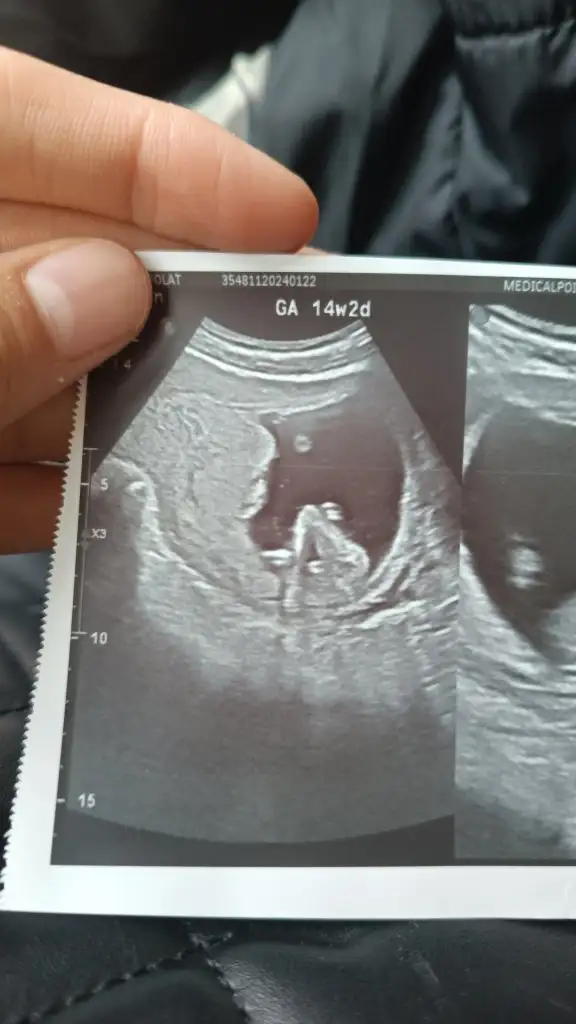

Hayır, benim bebiş utangaç biri sanırım, ısrarla göstermedi ve uyudu 😁 eğer gösterirse haftaya öğrenicez inşallah 🤗 tahmin ederim derseniz 13+4 ten ultrason görüntüsü 😁

Hadi ya bizimki de uykucu tok ve boş su iç idrar sıkışık gel dedi sizinde yatıyor hiç nub bile belli degil tüh anlaşılmıyor cidden

Çocuk tüm çabalara rağmen 2 kere hareket etti, ilkinde ayaklarını başına götürdü dümdüz, bacaklarını esnetti sonra kıvrıldı yine. En son da el salladı geri uyudu. Önümüzdeki randevuya tok karınla gidicem, güzelce kahvaltımı yapıp, çikolatamı yiyip, sodamı içip, 2 lt su şişemi alıcam yanıma. Yeter artık herkes cinsiyeti öğrendi, kutlamasını yaptı, alışverişine başladı, biz 15 hafta bitecek çocuğun cinsiyetinden bi haberiz yahu 😂